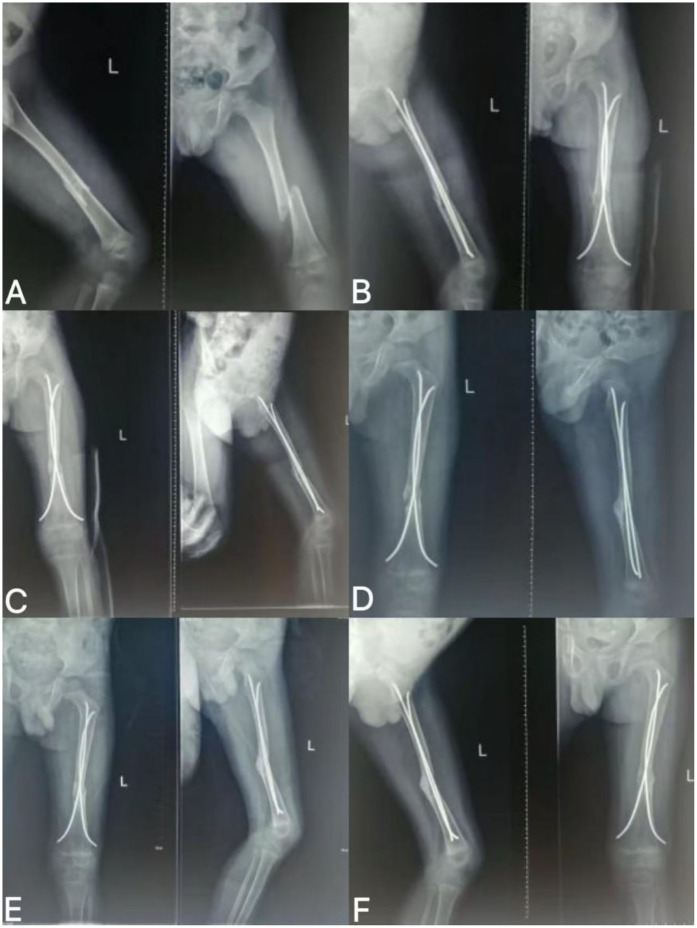

Methods: A 4-year-old male with left femoral shaft fracture (AO/OTA 32A2) and FDA-defined nonunion 9 months after FIN fixation received rESWT. Using Gymna ShockMaster 300 (Uniphy), parameters were 6-8 Hz, 2.0-3.0 bar, 1,000-1,500 pulses/week for 3-4 weeks (covering fracture and 2 cm around). Treatment included pre-procedural screening, professional operation, gamified communication, and concurrent rehabilitation.

Results: Post-rESWT, fracture lines blurred then disappeared, with clinical healing achieved and no complications. At 3-month follow-up, intramedullary nail was removed; the patient had 80% weight-bearing capacity, independent walking (mild gait asymmetry), and full weight-bearing recovery later.